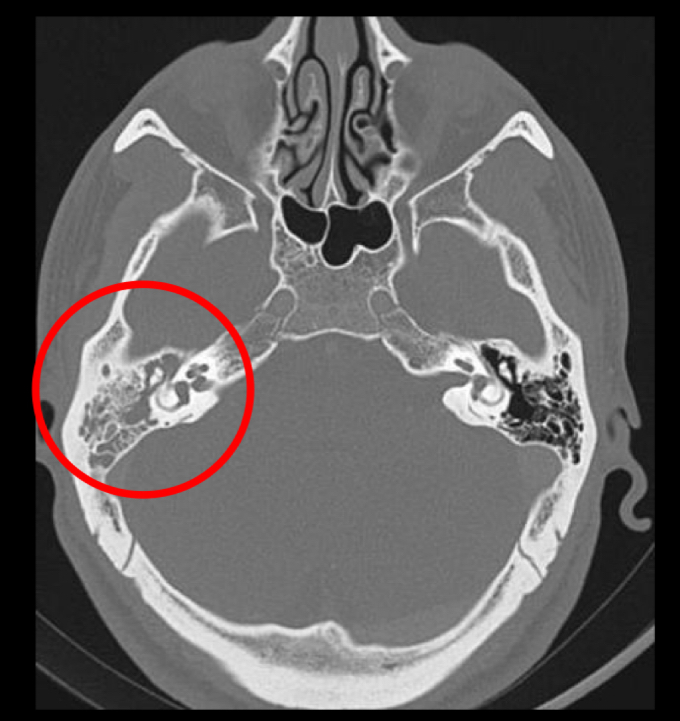

mejor estudio dx

A

tc

q se ve en tc

opacificacion de celdillas mastoideas mas coleccion

Cronico: esclerodiploico(engrosamiento oseo)

como se ven los abscesos en tc opacificacion

pueden involucrar ECM(BEZOLD)

Pueden extenderse a fosa posterior y fosa craneal media